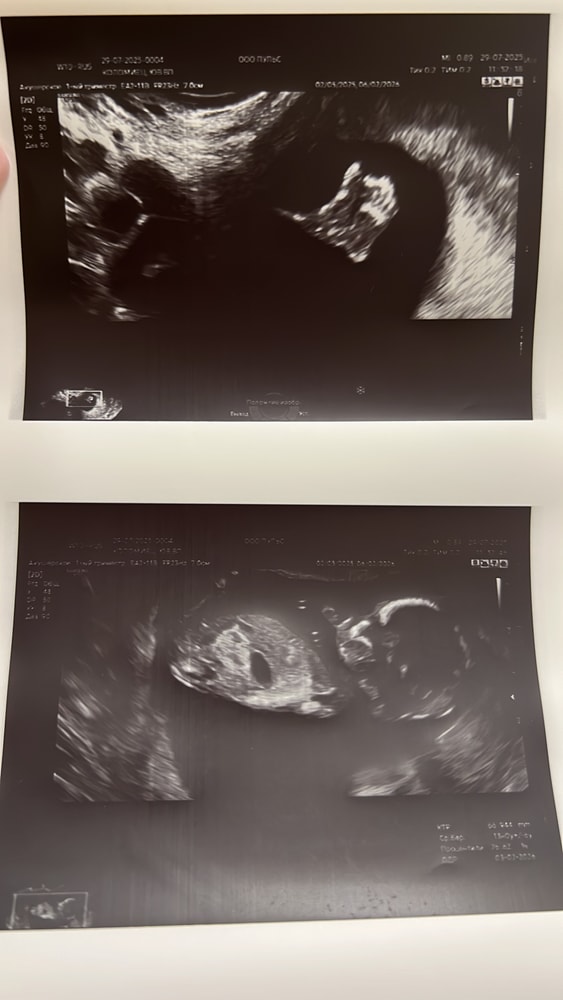

Результаты УЗИНаконец-то я в своей беременяшковой суете добралась рассказать, как у нас дела и как мы растем❤️🥹👶🏻

Малышарик растет🙏чуть опережаем тьфу тьфу срок, кстати выставляют и будут корректировать срок по скринингу, сказано так. Скрининг 1 триместра прошли, все отлично за исключением ВАЖНО кровотоки МПК нарушены ПИ было 2,8 и 2,3. Сразу же приняты оперативно меры по терапии Актовегин, Курантил, Кардиомагнил и Клексан дружно со мной - итог по узи 04.08. кровоток улучшился ПИ 2 и 1,9🙏 далее смотримся 12.08. Риск эклампсии 1 из 4 😬🤪 но с моим анамнезом я не паникую тут главное контроль над ситуацией и стабильность. Спасибо и низкий поклон всей команде врачей РКБ г. Казани, что они с нами на пути к нашей большой мечте - рождению Крохи❤️🙏

Естественно не обошел меня и ГСД, ну ничего страшного, датчик/инсулин и все под контролем. Еще о важном 😍 - Наша трёхдневочка - Сынуля👶🏻 Наш сильный любимый Малыш👶🏻